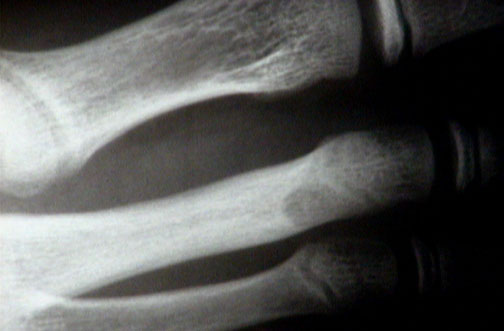

Click on the osteoid osteoma in the radiograph above:

This is the central nidus of an osteoid osteoma. Radiographically, there is a small round central lucent area in the metatarsal bone cortex surrounded by sclerotic bone.